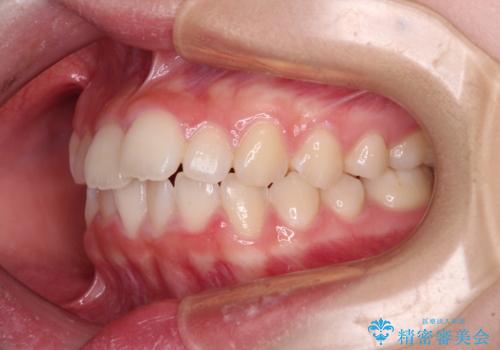

上下ともに少し捻れが残っていたため、治療の継続を提案しましたが、本人も親御さんも満足とのことで、治療を終えました。

捻れの改善により突出感も改善されました。